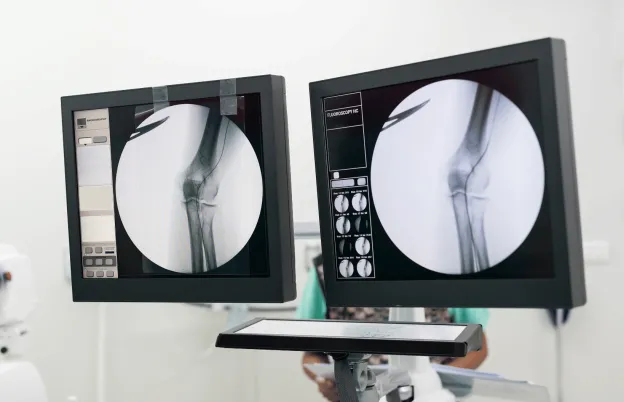

- Hoffa’s fat pad